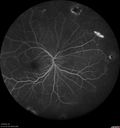

Grade 4 hypertensive retinopathy485 views55 year old man Hhe did have headaches a few weeks ago and also some nausea and vomiting. He noticed for a few weeks the vision in the left eye was blurred and that the vision in the left eye is dark.

VA OD: Dcc20/20

VA OS: Dcc20/100-1

He was admitted directly to ICU for blood pressure control (290 / 170 mmHg)

3 weeks later his VA increased to 20/20 OD, 20/32 OSJan 29, 2019